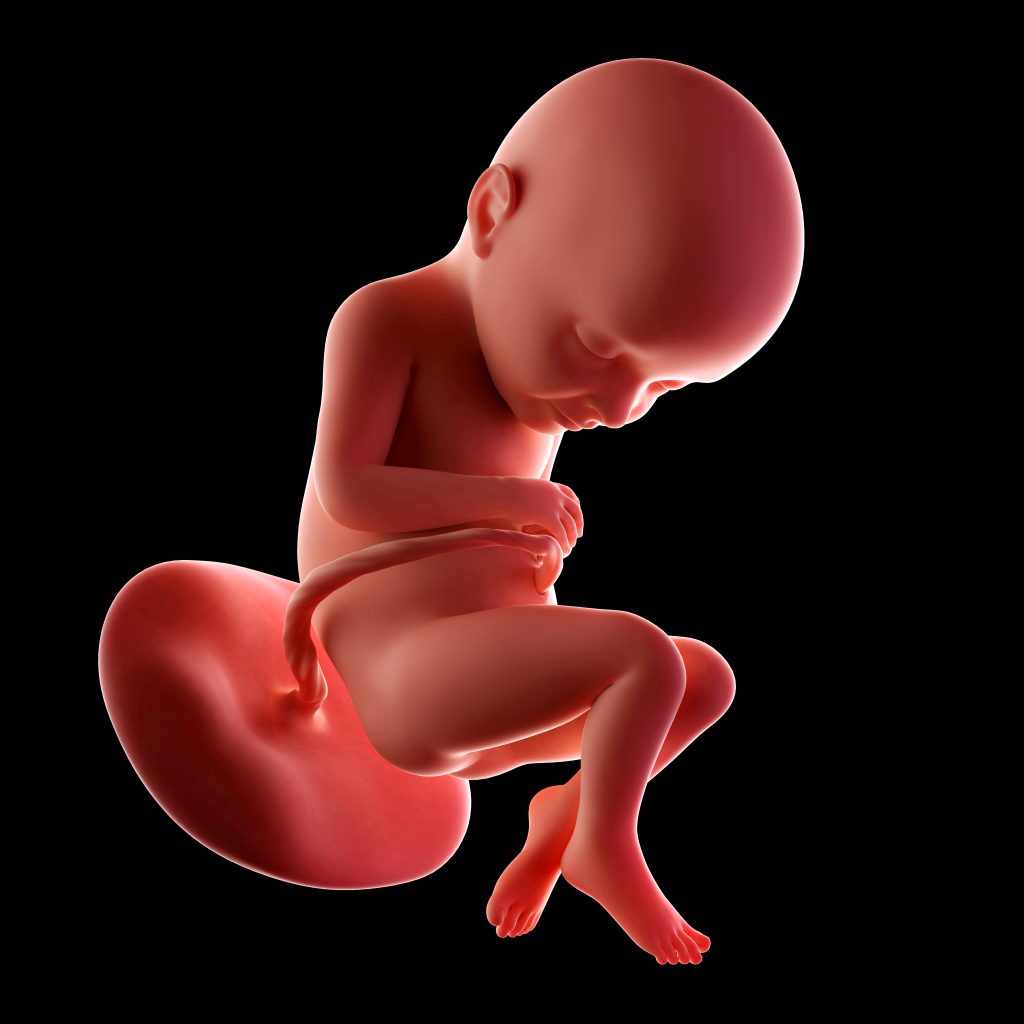

Alles over je baby

Maand 8 Zwangerschap week 31 t/m 35

Alle vijf de zintuigen zijn in week 31 ontwikkeld en volop in gebruik. Je kunt je kindje flink voelen bewegen. Hij of zij is waarschijnlijk met name actief als je zelf lekker op de bank of in bed ligt. Ook kan je kindje de hik hebben. Je herkent dit aan een ritmische kleine beweging in je buik. Het is volledig onschuldig, net zoals bij onszelf. Veelal ontstaat de hik als gevolg van uitzetting van de maag. Grote kans dat je kleintje dus net gulzig van het vruchtwater heeft gedronken.

Besefmomentje: je bent al ruim op driekwart van je zwangerschap! Als je uitgaat van een voldragen zwangerschap dat zal je kindje nog zeker verdubbelen in gewicht.

41 cm

1500 g

Week 32

Alle botten in het lijf van je kindje worden steeds harder, zo ook de schedel. De schedel bestaat uit verschillende onderdelen, waartussen zich naden bevinden. Deze groeien nog niet dicht. Dat is maar goed ook, want tijdens de geboorte kunnen de schedelvlakken over elkaar schuiven zodat het hoofdje door het geboortekanaal past. De kans is nu – bij pakweg 32 weken – al vrij groot dat het kindje al met zijn of haar hoofdje naar beneden ligt. De kans op draaien wordt al wat kleiner. Wel kunnen ze tot het einde van de zwangerschap nog met hun rug van links naar rechts draaien. Dat maakt ook niks uit. De positie van het hoofdje in je bekken is nu nog niet van belang. Pas tijdens de bevalling (wanneer er ontsluiting komt) kan het hoofdje verder indalen in je bekken en wordt het belangrijk welke kant het hoofdje op gaat draaien. Die draai (de zogenaamde spildraai) kunnen ze nog heel lang maken; zelfs nog tijdens het laatste deel van de bevalling. In onze module over bevallen laten we dit graag aan je zien!

42 cm

1800 g

Week 33

In deze week verdwijnen de donshaartjes steeds verder. Het spijsverteringsstelsel en de nieren functioneren nu zelfstandig. Je kindje plast ongeveer een halve liter per dag in het vruchtwater. Het vruchtwater wordt opgedronken en daarmee slikt hij ook de donshaartjes in die los gelaten hebben. Deze prikkelen de darmen, waardoor de ontlasting op gang komt. De eerste ontlasting van je kindje heet meconium en heeft een groen-zwarte kleur. De meeste kindjes poepen pas na de geboorte, maar een deel poept ook al in het vruchtwater. Als dat zo is kom je hier pas achter als de vliezen breken (het vruchtwater is dan groen of bruin van kleur). Dit is een reden om in het ziekenhuis te bevallen. Hierover vertellen we je meer in onze cursus.

43 cm

2000 g

Week 34

Vanaf week 34 tot aan de geboorte komt je kindje nog zo’n 200 tot 250 gram aan per week; een ware groeispurt dus. De groei komt met name door de toename van bruin vet, hetgeen het kindje warm houdt. Het bevindt zich bovenaan de rug en in de schouders van je kindje. Nog een weetje: bij jongetjes zijn de balletjes nu meestal helemaal ingedaald. Mocht je nog een echo krijgen dan kan je dit al zien.

44 cm

2200 g

Week 35

Ook in week 35 blijft het belangrijk de bewegingen van je kindje goed in de gaten te houden. Het ritme wordt steeds duidelijker, waardoor veel vrouwen ervaren dat hun kindje op dezelfde momenten van de dag rustiger en drukker is. Door het gebrek aan ruimte kunnen de bewegingen wel degelijk veranderen: het wordt meer schuiven of draaien in plaats van schoppen en stompen. De frequentie hoort echter wel gelijk te blijven. Beweegt je kindje minder dan je gewend bent, trek dan aan de bel en laat een extra controle uitvoeren.

Het is nu ook belangrijk dat het kindje met het hoofdje naar beneden ligt. Als het uitwendig niet met zekerheid te voelen is, wordt om deze reden een echo gemaakt. Ligt het kindje niet met het hoofdje naar beneden, dan kun je een zogenaamde uitwendige versie laten uitvoeren. Hierbij wordt geprobeerd het kindje te draaien. Als je dit niet wilt of de versie lukt niet, zal er gesproken worden over de opties bij een stuitligging. Alle ins en out die komen kijken bij stuitligging komen aan bod in onze cursus. In een speciale bonusmodule leggen we je alles uit over (verschillende soorten) stuitligging, een versie en de verschillende manieren van geboorte met de voor- en nadelen.

45 cm

2500 g